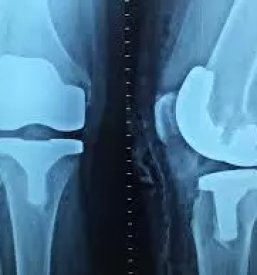

Ukvarjamo se z zdravljenjem težav s področja ortopedije, kot so težave s koleni, ramo, zapestjem, hrbtenico in podobno. Izdelujemo izvedeniška mnenja in sodelujemo pri raziskavah na tem področju. Dodatno v naši ponudbi najdete tudi prodajo ortopedskih pripomočkov.